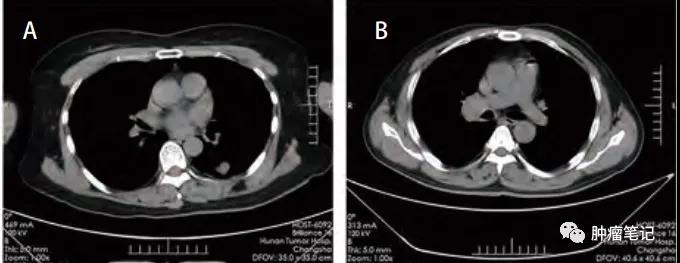

影像学

肺淋巴上皮样瘤样癌有一定的特征性,有些学者的报道并不完全一致,可能与样本量较少有关。

Ooi等认为晚期LELC,肿瘤可表现为直径大、边界清晰,与纵隔密切相关,且伴有支气管血管周围淋巴结转移和血管包绕。

Hoxworth等,认为肺淋巴上皮样瘤样癌主要表现为胸膜附近的孤立性肺结节,体积<3.5 cm,通常不累及淋巴结。

Ma等报道肺淋巴上皮样瘤样癌的CT表现包括界限明确、分叶、血管或支气管包裹、阻塞性肺炎、胸腔积液和钙化,在右中叶和左下叶更常发生。